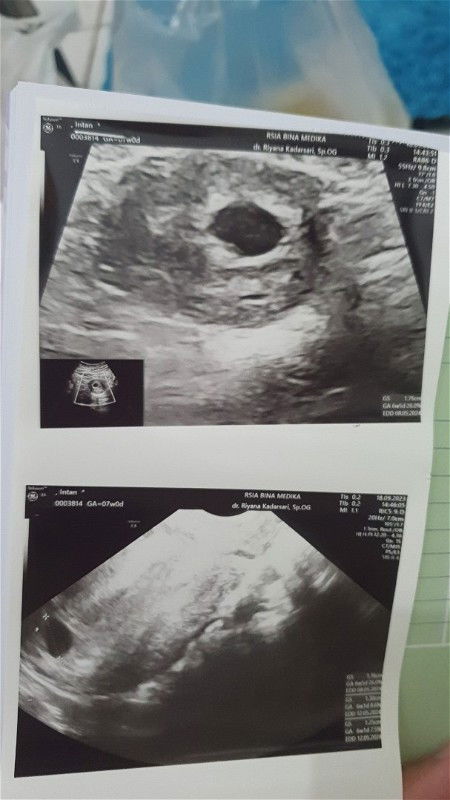

Hamil 6week 5hari baru terlihat kantung janin

Moms mau tanya ini aku hamil pertama, usianya 6week 5 hari kemarin pas di usg baru terlihat kantung janin aja, ada yang sama ga ?

alhamdulilah kemaren aku 6w1d udh ada janin & detak jantungnya